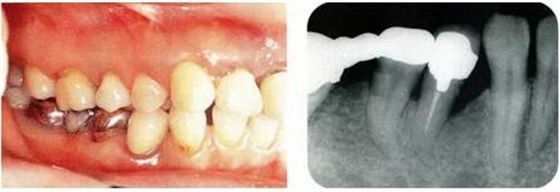

病例5使用正畸進(jìn)行牙齒挺出,讓骨平坦化:

圖18-1(左),2 (右)▲初診時(shí)口腔內(nèi)照片和X線片,右下4近中有較深的1壁性骨缺損,右下45有根接近。如果在這個(gè)情況下進(jìn)行骨外科處理,需要犧牲較多的右下3遠(yuǎn)中的牙槽骨。也會(huì)造成周圍骨形成較大的臺(tái)階。